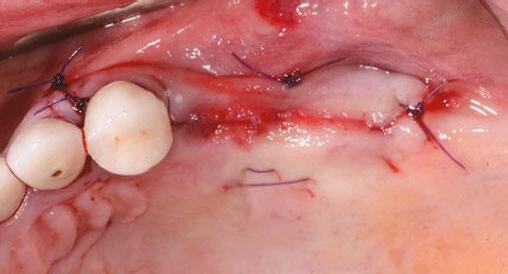

Let’s review a recent case that showcases the rationale and techniques of the top three. It is common to utilize several suturing techniques in surgical closure, especially in larger grafting cases. In the following case, a lateral sinus lift was performed, and all three techniques were used to their full effect. Simple interrupted sutures are used to close small incisions and place tissue margins accurately back in place; horizontal mattress sutures are used to hold membranes in place and relieve tension over the incision line, and running interlocking continuous sutures are used to close longer incisions with watertight closure for maximum healing potential via primary closure.

A patient presented with a failing bridge on the upper left that is supported by three mini implants. The implants directly perforate the sinus and only ~2mm of residual bone height remains on the crest (Figure 8). The mini implants were removed, and a

Figures 7A and 7B: Horizontal mattress sutures are useful for helping to secure membranes in grafting situations and relieving tension in longer span incisions Figures 8A and 8B: The pre-op condition of the patient with mini implants engaging minimal bone and perforating the sinus. The patient’s implant supported bridge was loose and causing discomfort Figure 9: A periosteal biting mattress engages only the periosteum in the buccal vestibule and exit and re-enters on the lingual tissue, helping to secure the membrane tightly over the window and crest